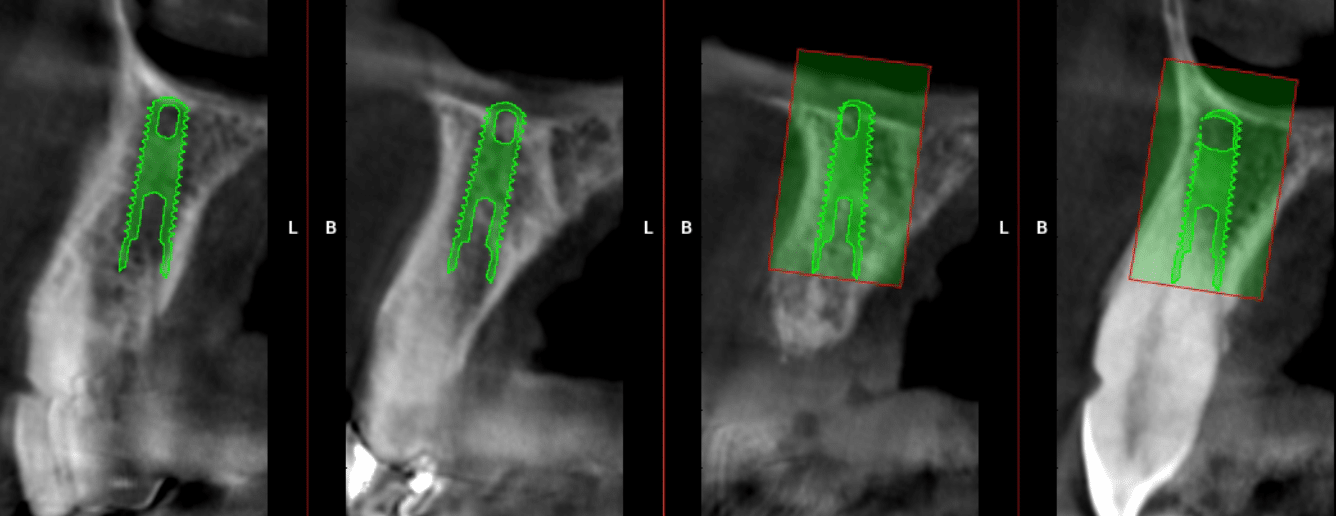

Le projet chirurgical permet d’envisager d’extraire l’ensemble des dents maxillaires et de placer six implants entre 15 et 25 pour la réalisation d’un bridge transvissé de 12 éléments :

La pose des implants devra (et pourra) être précédée d’une résection osseuse verticale suffisante après les extractions afin de remonter la ligne de transition implanto-prothétique à la limite du découvrement de la lèvre pour assurer un sourire plus esthétique. C’est ce dernier point qui décide la patiente à accepter ce plan de traitement de restauration globale.

Dans ce cas, la pose des implants a été réalisée sans guide chirurgical : ce sont les alvéoles déshabitées qui ont guidé les forages.